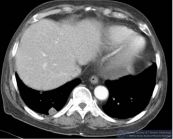

Thuyên tắc mạch phổi là căn bệnh thường gặp với tỷ lệ tử vong khoảng 30% nếu không được phát hiện và điều trị sớm. Để hiểu rõ hơn về bệnh lý này, mời các bạn cùng tham khảo bài viết ngay sau đây!